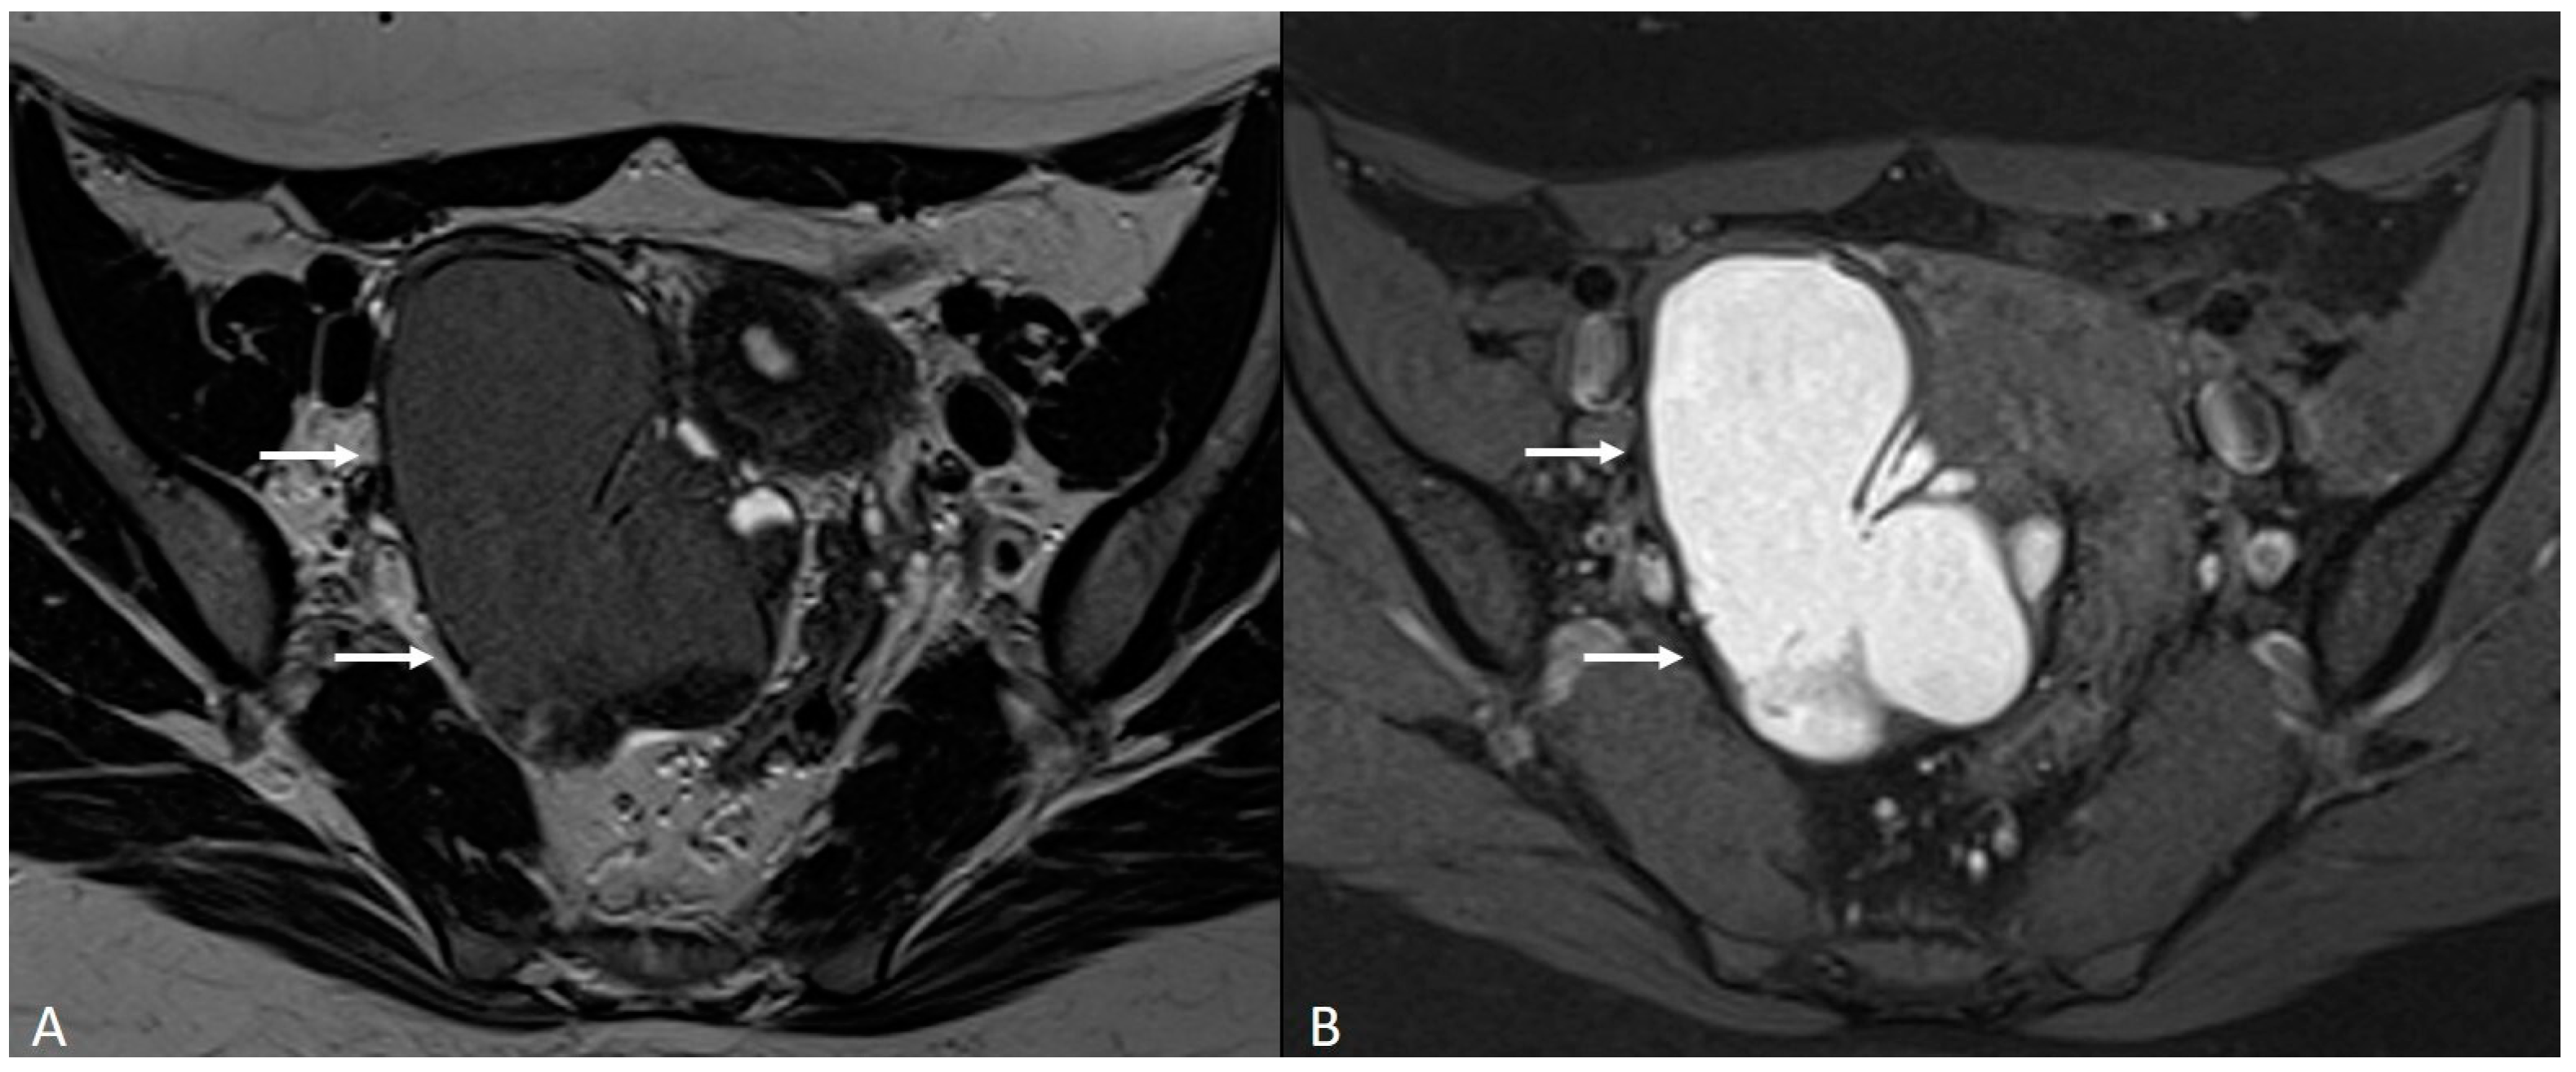

4. Ovarian Endometrioma

- Kido, A.; Himoto, Y.; Moribata, Y.; Kurata, Y.; Nakamoto, Y. MRI in the Diagnosis of Endometriosis and Related Diseases. Korean J. Radiol. 2022, 23, 426–445. [Google Scholar] [CrossRef]

- Dias, J.L.; Veloso Gomes, F.; Lucas, R.; Cunha, T.M. The Shading Sign: Is It Exclusive of Endometriomas? Abdom. Imaging 2015, 40, 2566–2572. [Google Scholar] [CrossRef]